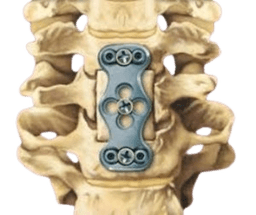

Spinal Fusion Surgery

Spinal Fusion Surgery involves joining two or more vertebrae to eliminate motion between them, providing stability and reducing pain from spinal instability or deformity. -br The procedure can treat conditions like spondylolisthesis, degenerative disc disease, or fractures. Bone grafts and implants such as rods or screws are used to facilitate fusion and long-term spinal alignment.